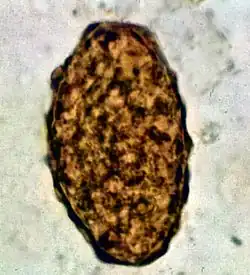

Fertile egg as can be seen in a microscope

Ascaris lumbricoides is characterized by its great size. Males are 2–4 mm (0.08–0.2 in) in diameter and 15–31 cm (5.9–12 in) long. The male's posterior end is curved ventrally and has a bluntly pointed tail. Females are 3–6 mm (0.1–0.2 in) wide and 20–49 cm (7.9–19 in) long. The vulva is located in the anterior end and accounts for about one-third of its body length. Uteri may contain up to 27 million eggs at a time, with 200,000 being laid per day. Fertilized eggs are oval to round in shape and are 45–75 μm (0.0018–0.0030 in) long and 35–50 μm (0.0014–0.0020 in) wide with a thick outer shell. Unfertilized eggs measure 88–94 μm (0.0035–0.0037 in) long and 44 μm (0.0017 in) wide.[9]